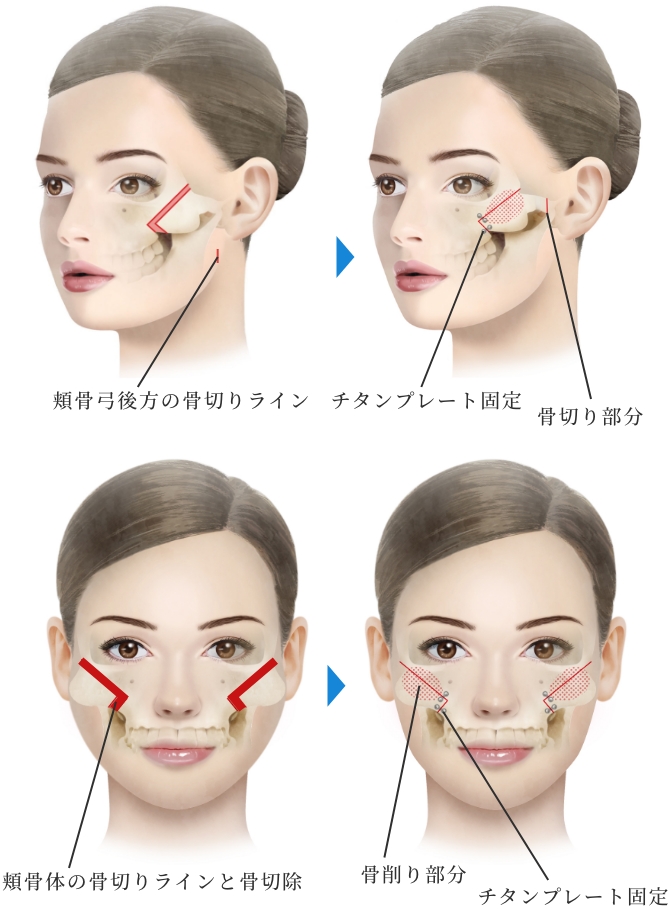

小木曽クリニックの

『頬骨形成骨切り術』の特徴

頬骨体部から弓(アーチ)

部に至る広範囲な骨切りが

可能

骨切り部位は頬骨弓部から体部前面に至り、L字型に長く幅広く切除し頬骨全体を内下方へ移動するため、頬骨全体に縮小効果があります。L字型に合計4回の骨切りが必要なため、複雑で精密な手技が必要な施術です。